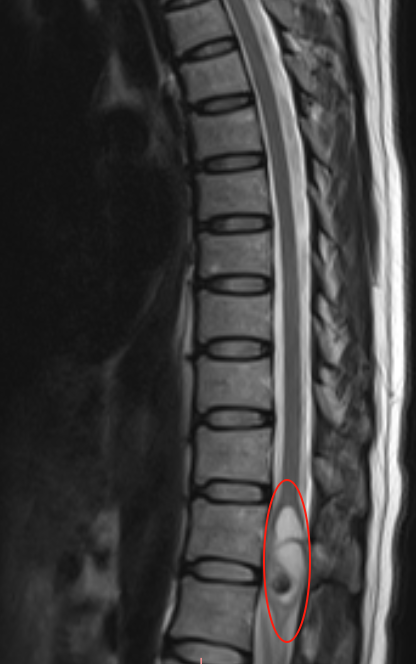

T12椎体水平脊髓圆锥内占位性病变,早期发现也是一种幸运!

43岁女性周女士患者2年间反复腰痛,MRI确诊T12髓内占位性病变。马尾有点像马的尾巴,神经血管丰富,手术复杂,术中稍有不当牵拉或双极电凝止血过度,就会引起脊髓梗塞,造成瘫痪、意识障碍、大小便障碍等严重并发症。

值得庆幸的是,周女士的肿瘤发现较早,体积尚小。与许多类似病例相比,她无疑是幸运的——很多患者在就诊时肿瘤已向脊髓上方扩散生长,治疗难度大大增加。”虽然目前情况尚不危急,但正是早期发现创造了治疗时机。“巴教授强调,”应该抓住这个幸运的机会。“